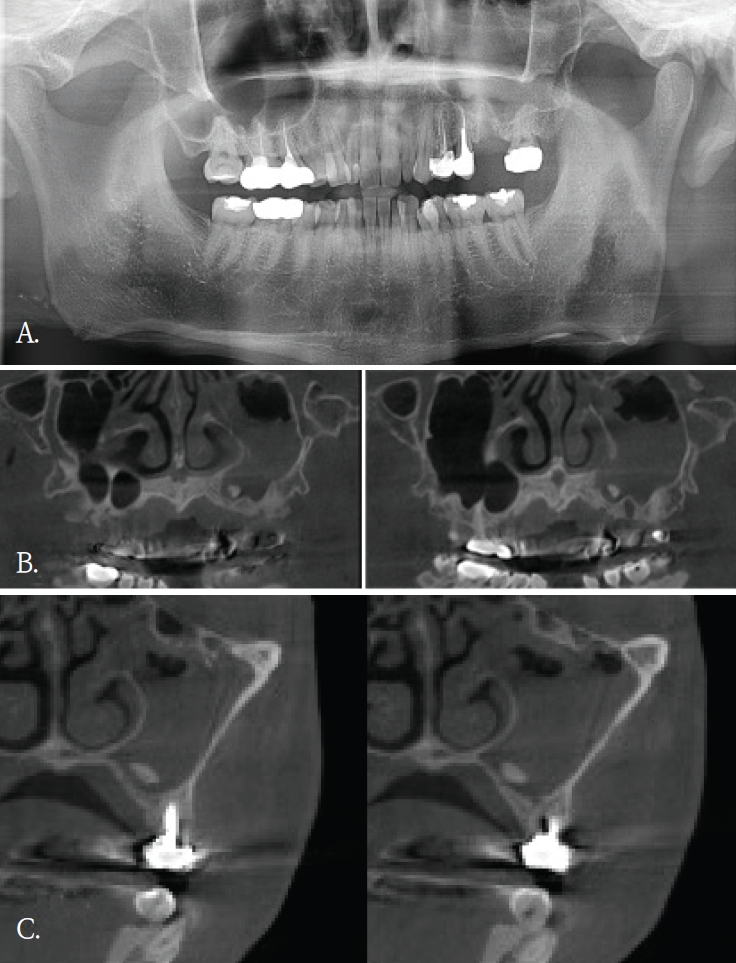

Fig. 4.

A. Panoramic radiograph shows an implant-shaped foreign body superior to the maxillary anterior region and appearing superimposed on the nasal cavity. B. Axial cone-beam computed tomographic (CBCT) image demonstrates that the foreign body is located in the labial soft tissue, without involvement of the nasal cavity. C. Cross-sectional CBCT image demonstrates that the foreign body is located in the labial soft tissue rather than in the maxillary anterior alveolar bone.

Fig. 5.

A. Panoramic radiograph. An extraction socket of the left maxillary first molar is noted. Diffuse haziness of the left maxillary sinus is observed; no other definite abnormality is identified. B. Panoramic reconstruction, C. cross-sectional cone-beam computed tomographic images. Soft-tissue density nearly fills the left maxillary sinus. A small radiopaque foreign body is identified at the floor of the sinus.

임플란트 식립 중 식립체가 시야에서 소실되어 위치 확인을 위해 60대 여자환자에서 파노라마방사선검사를 시행하였다. 파노라마방사선영상에서 임플란트 식립체로 추정되는 금속성 방사선불투과성 구조물이 우측 비강 부위에 중첩되어 관찰되었고 영상에서 비강 하연 부근에 위치한 것처럼 보였다(Fig. 4A). 이에 비강 및 상악 치조골과의 정확한 위치 관계를 평가하기 위해 콘빔CT 검사를 시행하였다. 콘빔CT에서 해당 구조물은 고음영 금속성 구조물로 확인되었으며, 상악 우측 전치부 측와 부위의 순측 연조직에서 관찰되었다(Figs. 4B and C). 또한 비강저 및 상악 치조골 피질골의 연속성이 보존되어 구조 발치와가 관찰되었다(Fig. 5A). 이러한 소견은 좌측 상악동 점막의 염증성 변화 가능성을 시사하였다. 상악동 병변의 범위 및 발치와와 상악동하연의 관계를 평가하기 위해 콘빔CT검사를 시행하였다. 콘빔CT에서 좌측 상악동 내에 연조직음영에 의한 혼탁이 관찰되었으며, 이는 상악동의 약2/3이상을 채우는 양상이었고 상악동 소공주변까지 연장되어 보였다. 또한, 상악동 전하방에서 경계가 명확한 작은 타원형의 균질한 고음영 구조물이 관찰되었으며, 골밀도에 해당하는 방사선불투과성 이물질로 판단되었다(Figs. 5B and C). 해당 고음영 소견은 파노라마방사선영상에서는 명확히 구분되지 않았다. 환자의 발치 병력을 고려할 때 해당 구조물은 상악동 내로 이동한 잔존치근이 의심되었으며, 외과적 제거를 시행하였다. 제거된 이물질은 상악동 내 잔존 치근으로 확인되었다.